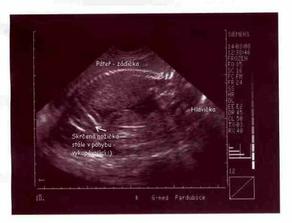

10.1.08 Další kontrola s ultrazvukem, miláček je krásně živej, všechno OK. 11.2.08 Kontrol proběhlo více, všechny víceméně v pořádku ... máme za sebou krevní testy, triple testy ... malý háček se objevil v maminčině krevní skupině rh- , ale snad bude vše v pořádku, testy na protilátky jsou negativní. Jinak mě začínají tlačit kalhoty, což asi znamená adios malému bříšku, ... welcome hrošíku 🙂 už přes týden cítím většinou večer malé motýlky a pomalu se vrhám na střádání výbavičky. Pěkně to utíká 🙂 7.3.08 Lékaři mě začínají trošičku děsit ... Prý jsme nějak menší, než je normální ... zhustila se frekvence prohlídek a hrozí mi kontrolka. 14.3.08 Screening ve 20 týdnu jsme absolvovali ve 21+1, jsme drobnější, ale jinak funguje vše, vše správně. Jen se nepodařilo odhalit, jestli Denis nebo Juli 🙂 24.4.08 3D utz v Hradci Králové, všichni byli milí, jen mrňousek bude prostě obrovskej stydlín ... ale pan doktor mi alespoň konečně prozradil, že to bude stydlivka Julinka 🙂 🙂 mám radost. A taky jsme se poprvé dozvěděli kolikvážíme ... celých 1060 gramů. 29.5. obvyklá prohlídka u gynekologa, už po dvou týdnech 🙂 Paní doktorka neustále straší, že mám malé bříško a poslala mě do nemocnice na dopllera. Mělo by to být vyšetření průchodnosti cév, prokrvení placenty. Pan doktor sice prohlásil, že Juli je menší, ale placenta je pěkná a mně už se mu nechtělo vyprávět příběh o cyklu s ovu 19DC a ne 14DC, jak mi neustále počítají ... Už se hodně informujeme o možnostech porodu a všeho okolo, říkám, už aby to bylo za námi a Julis s námi :D (ani jsem si na zprávě skoro nevšimla, že nás pan doktor vážil, takže 32+6 má Julísek krásných 2240 gramíků > pořád nechápu, co se jim nezdá :D 27.6.08 další dopller, paní doktorce se pořád nezdá moje bříško a tak zase víme, že už Juli váží 2770 gramíků, průchodnost cév je v pořádku a vše ostatní taky, bude to prostě cvrček majinkatej, vzali jsme to i s prvním monitorem a ten byl taky velice v pořádku ... tak ještě pár dní a už se setkáme 🙂 30.7.08 Jak jsem se bála, že nás budou nutit a teď bych nevím co dala za to, kdyby nastala nějaká změna. Přes týden přenášíme a malá se stále k ničemu nemá. Kontroly v nemocnici dvakrát do týdne už mě opravdu začínají otravovat. V pondělí jsem dokonce okusila Hamiltona, ale nijak zvlášť to nepůsobí. Tak už pojď ven mrško 🙂